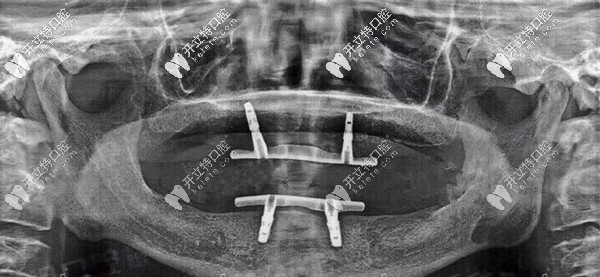

陳叔叔口腔檢查情況

▲陳叔叔口腔檢查情況

偶然間,家人聽(tīng)說(shuō)該口腔可以“當(dāng)天種牙、當(dāng)天用牙”,家人告訴了陳叔這個(gè)消息后,陳叔便欣喜的來(lái)到石家莊中諾口腔面診。陳叔叔全口種植牙前

▲陳叔叔全口種植牙前

經(jīng)過(guò)一系列口腔拍片檢查后,陳叔口腔適合立得用技術(shù)做全口種植,當(dāng)時(shí)就和家人一起跟醫(yī)生確定了方案以及種植時(shí)間。